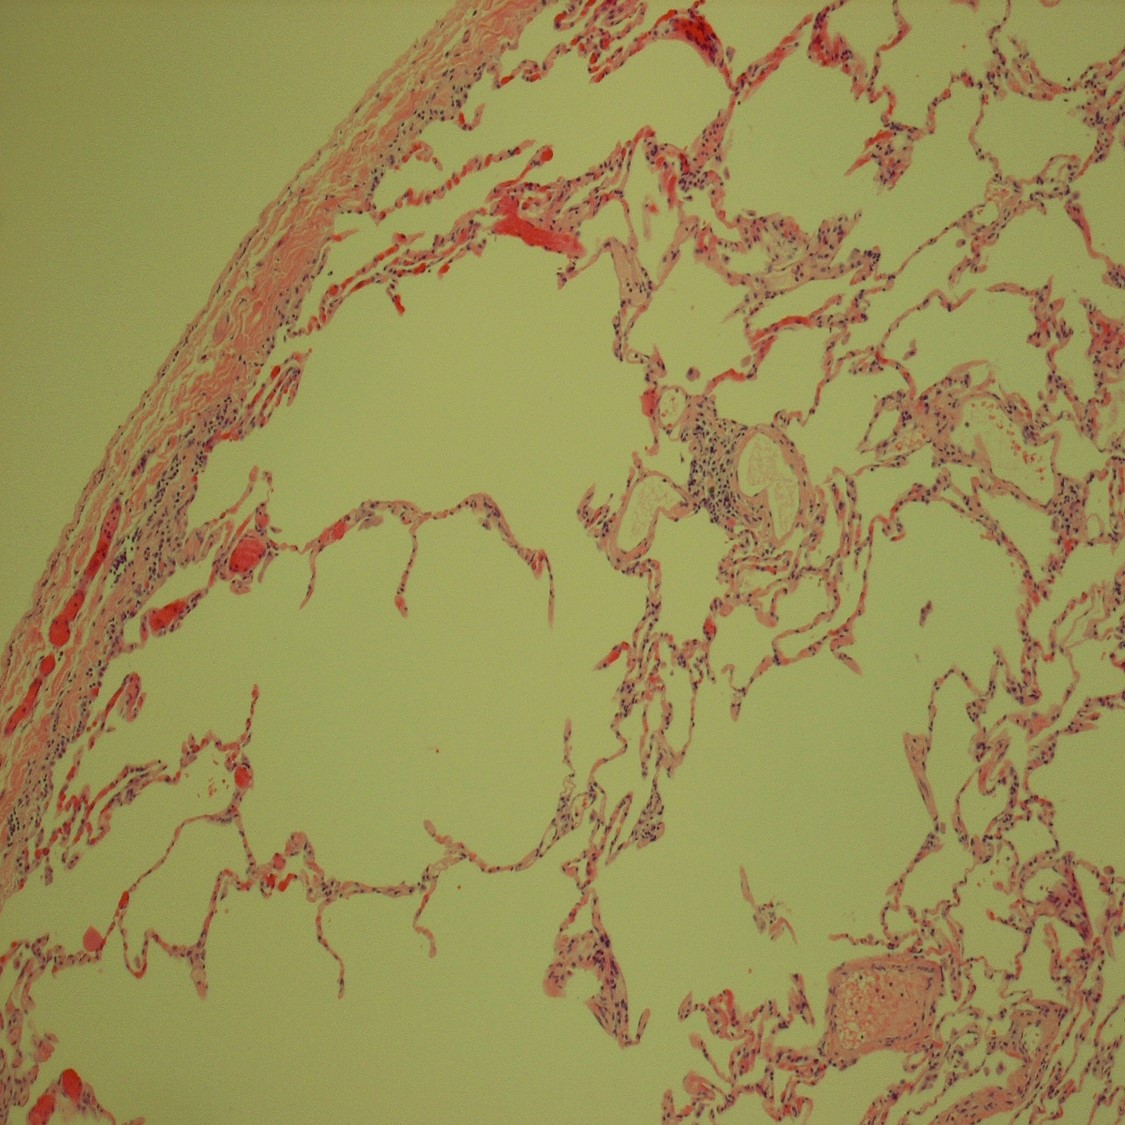

This 39-year-old Hispanic woman, a never smoker, underwent thoracotomy and...